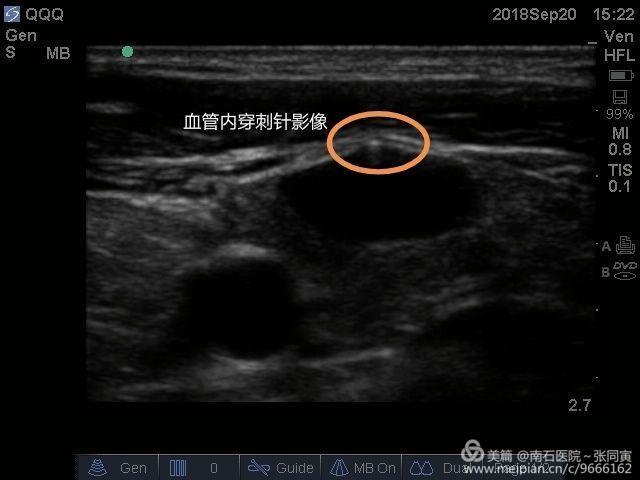

超聲引導(dǎo)下麻醉手術(shù)實(shí)踐,使麻醉進(jìn)入可視時(shí)代

南石醫(yī)院門(mén)診手術(shù)室購(gòu)買(mǎi)引進(jìn)床旁超聲儀,科室的童鞋們都喜出望外,將為科室添加一雙火眼金睛,以后的麻醉將全面進(jìn)入“可視時(shí)代”。